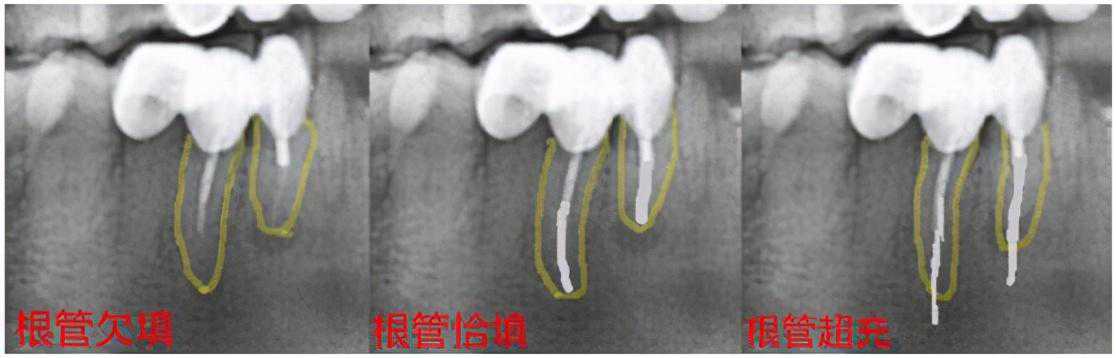

根管治疗遇到髓室底底穿,根管壁侧穿,根管充填欠填、超填,遗漏根管,断针,根管折断……等情况均可能导致根管治疗的失败。

(黄色线为牙根,白色线为根充物)

所有的治疗,都没有百分之一百的成功率,随着牙体牙髓学理论的进步,技术的发展,根管治疗的远期成功率,也只能无限的接近百分之一百。

因此,即便我们在根管治疗时,出现上述情况,也别太过于害怕,请相信你的牙医,他们会尽力避免上述情况的出现,一旦出现上述情况,仍有一定的补救手段可以使用。